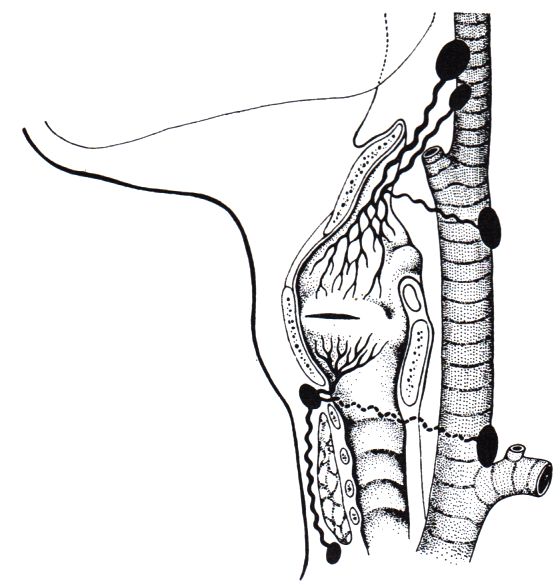

Im Bereich der Glottis sind sehr wenige Lymphegefäße. Die so pragmatischen Lymphebahnen führen zur vorderen jugulären Lymphknotenkette. Legefäße der Subglottis führen in prätracheale Lymphknoten der Mittellinie und seltener in untere zervikalen Lymphknoten.![]() | ||